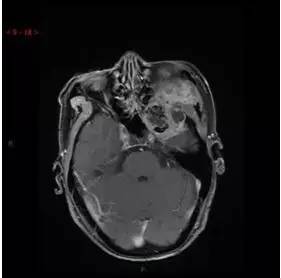

MRI增强轴位

MRI增强冠状位

MRI增强矢状位